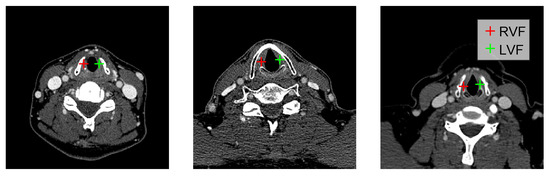

| LVF | Left vocal fold |

| RVF | Right vocal fold |

| RL | Reinforcement learning |